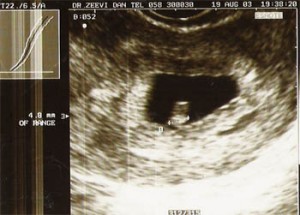

»5 тиждень вагітності. Перший триместр.

Зростання вашого дитинчати - 4-7 мм, вага - 3,5 м